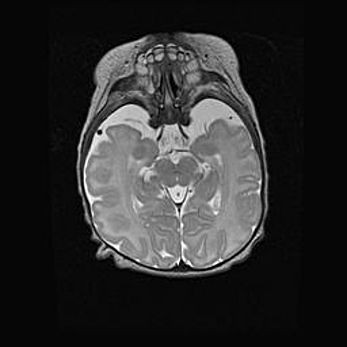

Множественные кисты обоих полушарий головного мозга, наибольшая из них в правой затылочной области. Ассиметричная атрофическая гидроцефалия.

Возраст: 7 месяцев

Вес: 5660 г

Пол: мужской

Окружность головы: 41,5 см

Срок гестации: 28-29 недель

Кисты головного мозга развиваются в результате многоочаговых некрозов вещества мозга и возникают вследствие перенесенной перинатальной инфекции, менингитов, энцефалитов, асфиксии, родовой травмы, расстройств мозгового кровообращения различного генеза. Образованию кист в веществе головного мозга плодов и новорожденных способствуют такие факторы, как высокое содержание в нем воды, недостаточная (или отсутствие) миелинизация и слабая астроглиальная реакция на повреждение.

Кисты могут сочетаться с гидроцефалией и другими поражениями головного мозга.